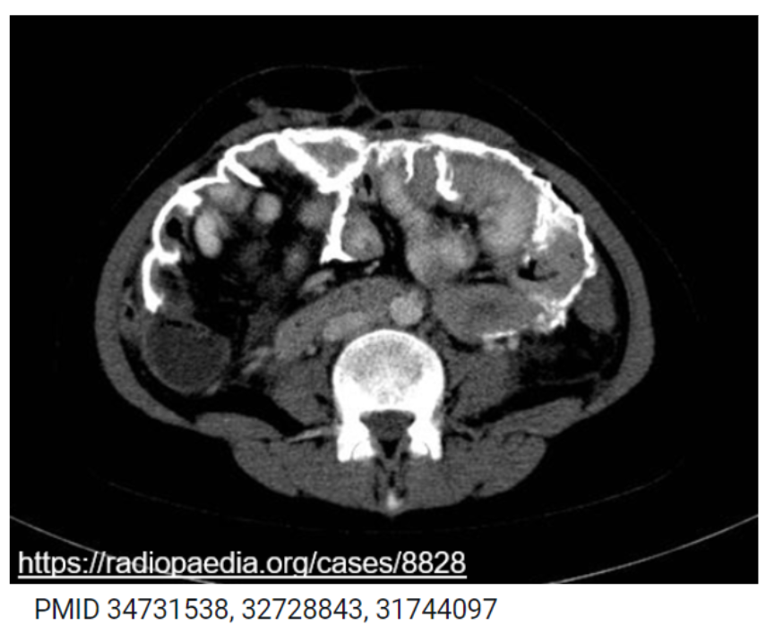

12/18 EPS is one of the most severe non-infectious complications.

Do you know how long it takes to develop EPS?

13/18 Ans: 5+yrs

Risk Factors:

📌long-term exposure to PD fluids

📌multiple/recurrent peritonitis bouts

📌genetic predisposition

📌meds: ex-practolol, chlorhexidine

Symptoms: severe abdominal pain, persistent n/v

Diagnosis: CT scan->cocooning of bowel & cystic fluid collections

14/18 Treatment of EPS: There is no standard treatment. PD is typically discontinued.

Early treatment with glucocorticoids, tamoxifen, immunosuppression may be useful

Symptomatic treatment: pain management, parenteral nutrition

PMID 31744097